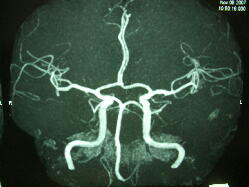

動脈瘤みつかる!

送られてきた結果をみると、MRAの結果に、「脳に動脈瘤があるかもしれないので精密検査を受けるように!」と書いてある。

上の画像のどこかに動脈瘤があって(シロウト目にはどこなのかわからない。。)、それが破裂すると「くも膜下出血」となって命にもかかわるが、破裂するかしないかはわからない。 予防策として動脈瘤をクリップで挟んで留める手術や、コイルを動脈瘤の中に詰め込む方法があるが、それにも危険性が伴う。 人間ドックの先生に相談した結果、動脈瘤も大きくない(3ミリくらい)し、定期的にMRAを受けていって、大きくなってくるようならば手術することで様子を見ることにした。